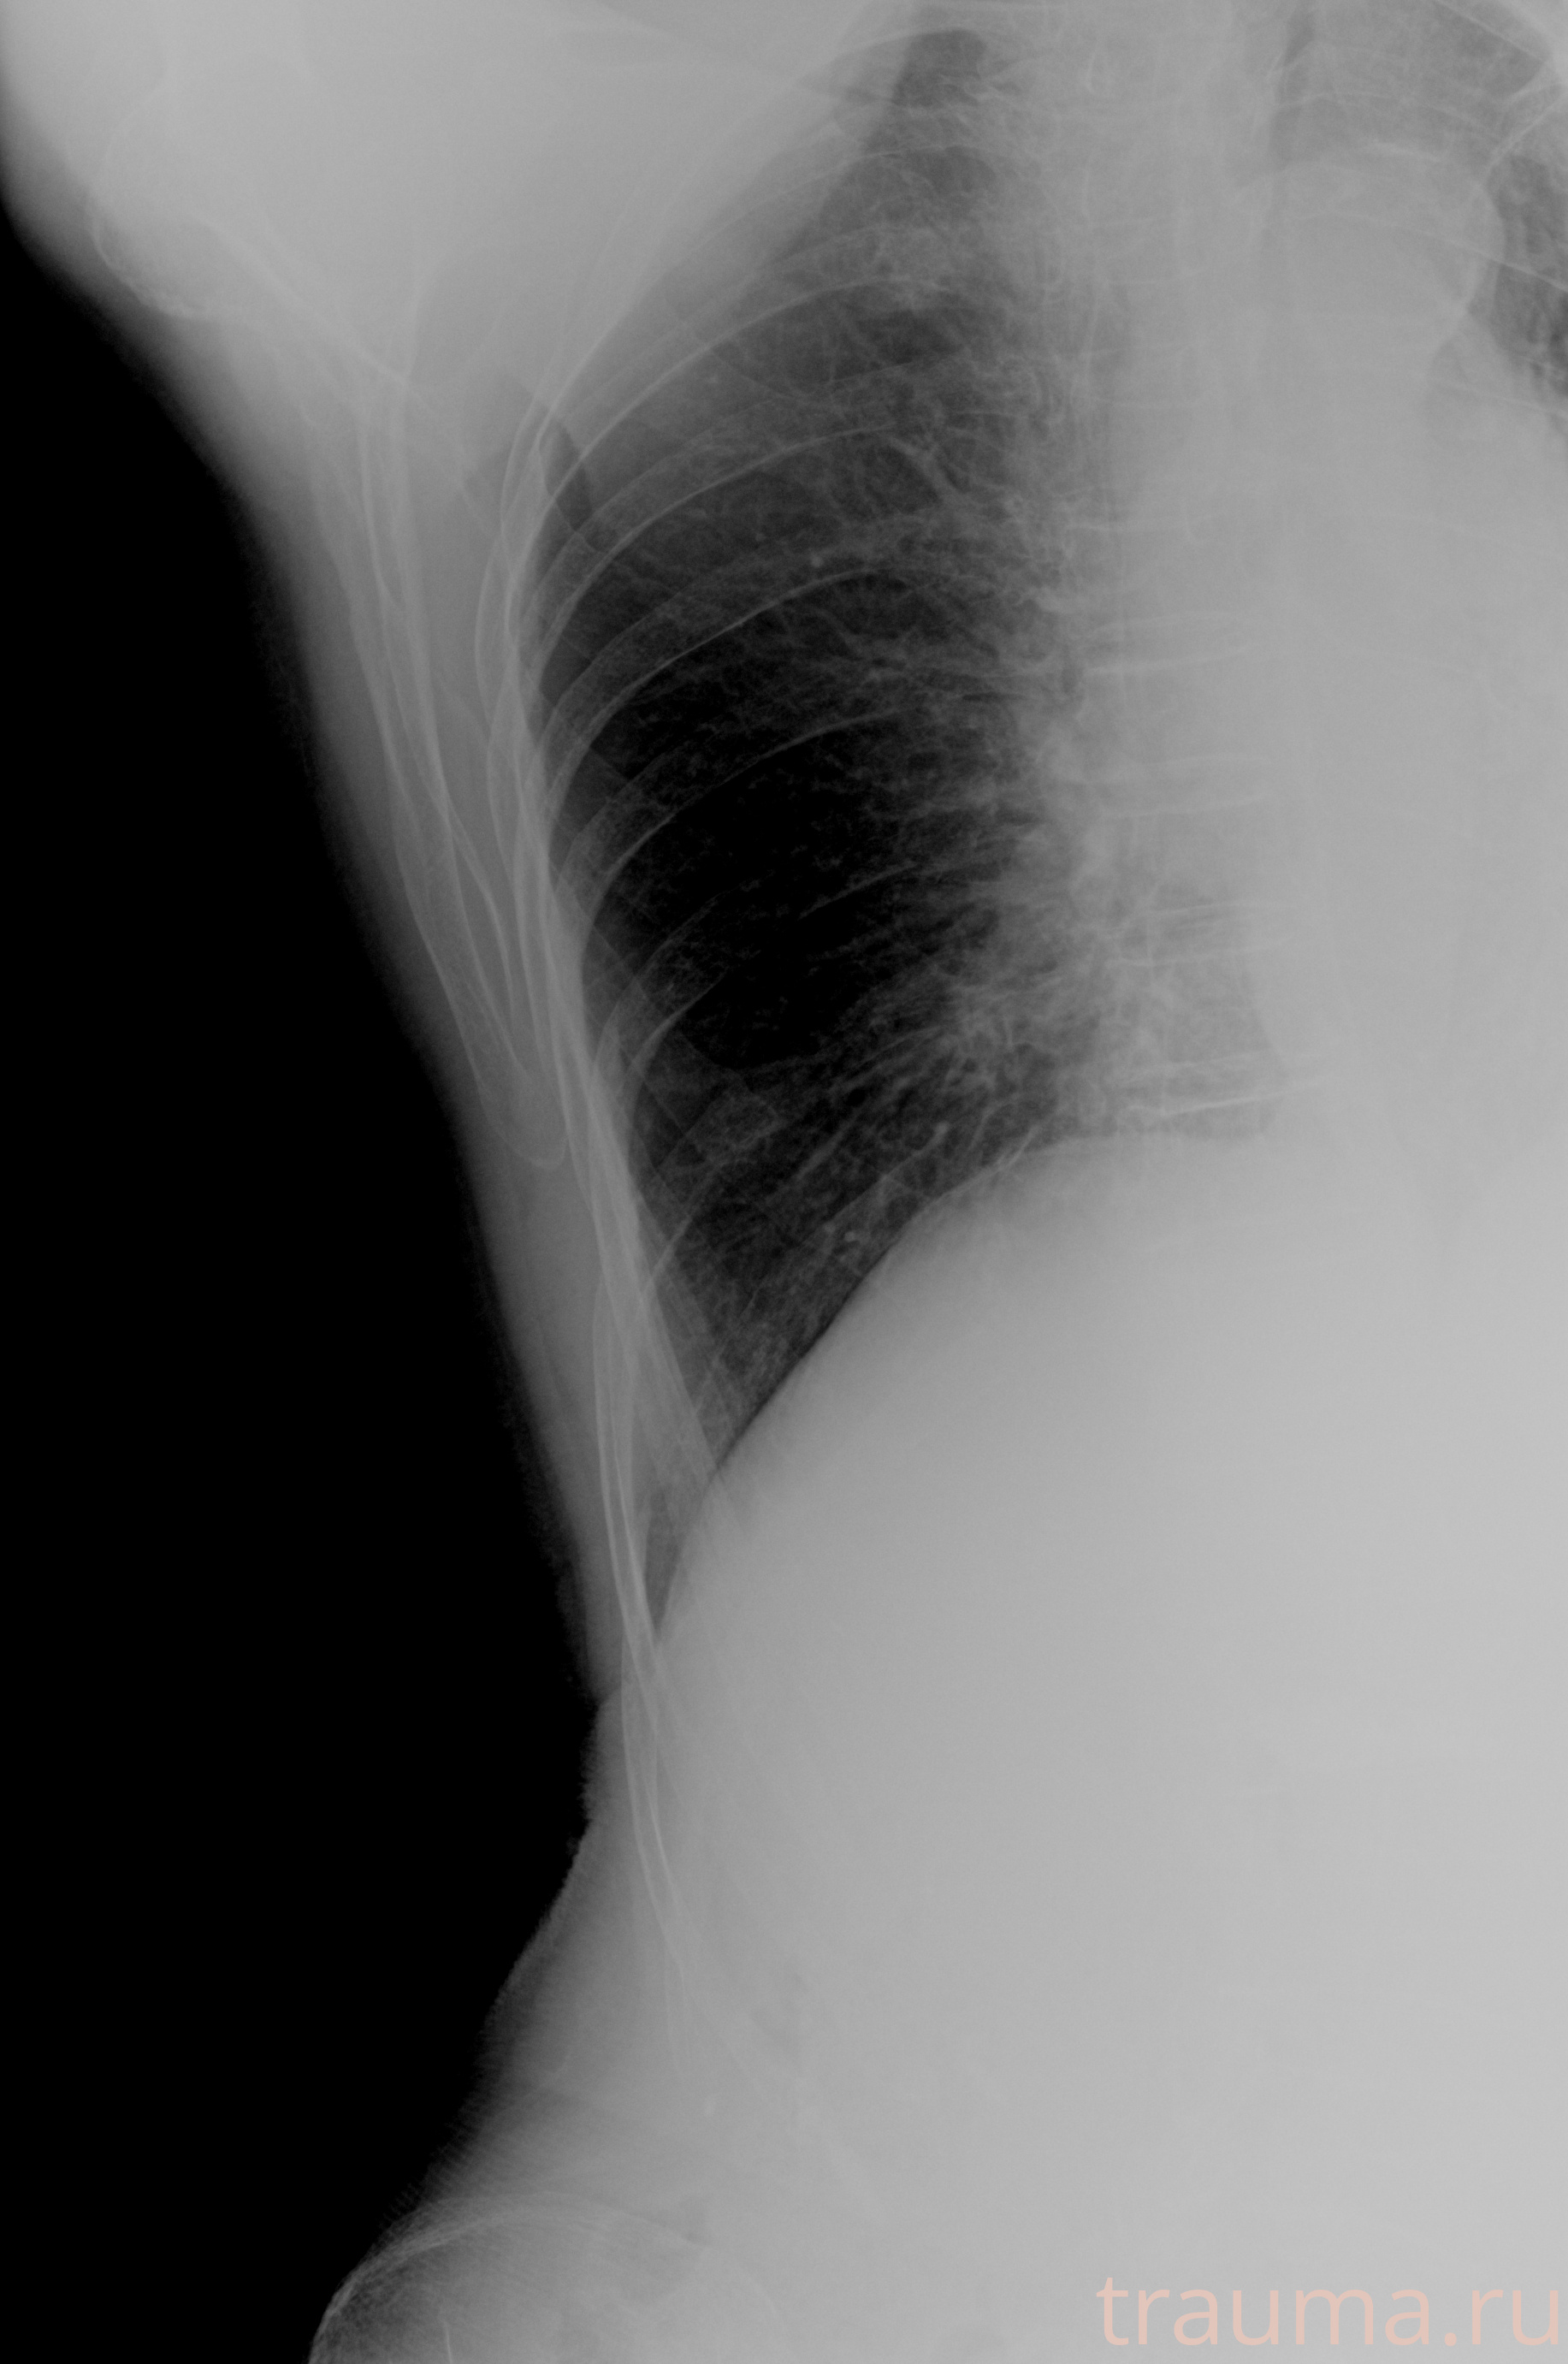

Рентгенограммы

Рентген на дому: по вашему адресу приезжает врач-рентгенолог, травматолог-ортопед с мобильным рентгеновским аппаратом, проводит диагностику травмы или заболевания, делает необходимые рентгенограммы, дает рекомендации по дальнейшему лечению. Получить качественные снимки в домашних условиях возможно благодаря уникальной методике, разработанной МосРентген Центром для института  Склифосовского

при переломе шейки бедра и пневмонии от компании МосРентген Центр - партнера Института имени Склифосовского